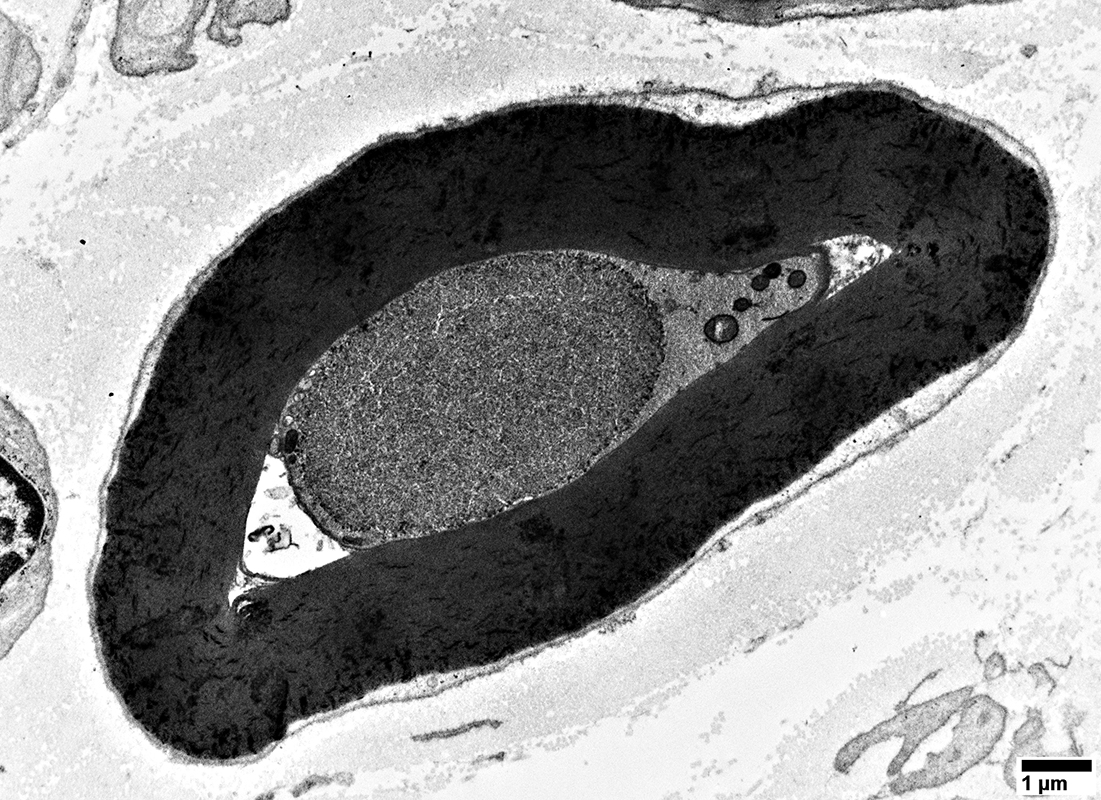

Axon, Intermediate-sized, Probably regenerating, within a set of Büngner band Schwann cell processes

With many mitochondria in axoplasm

Surrounded by multiple Schwann cell processes (?

Büngner band)

Fibroblast process outside of Schwann cell processes (Upper left)